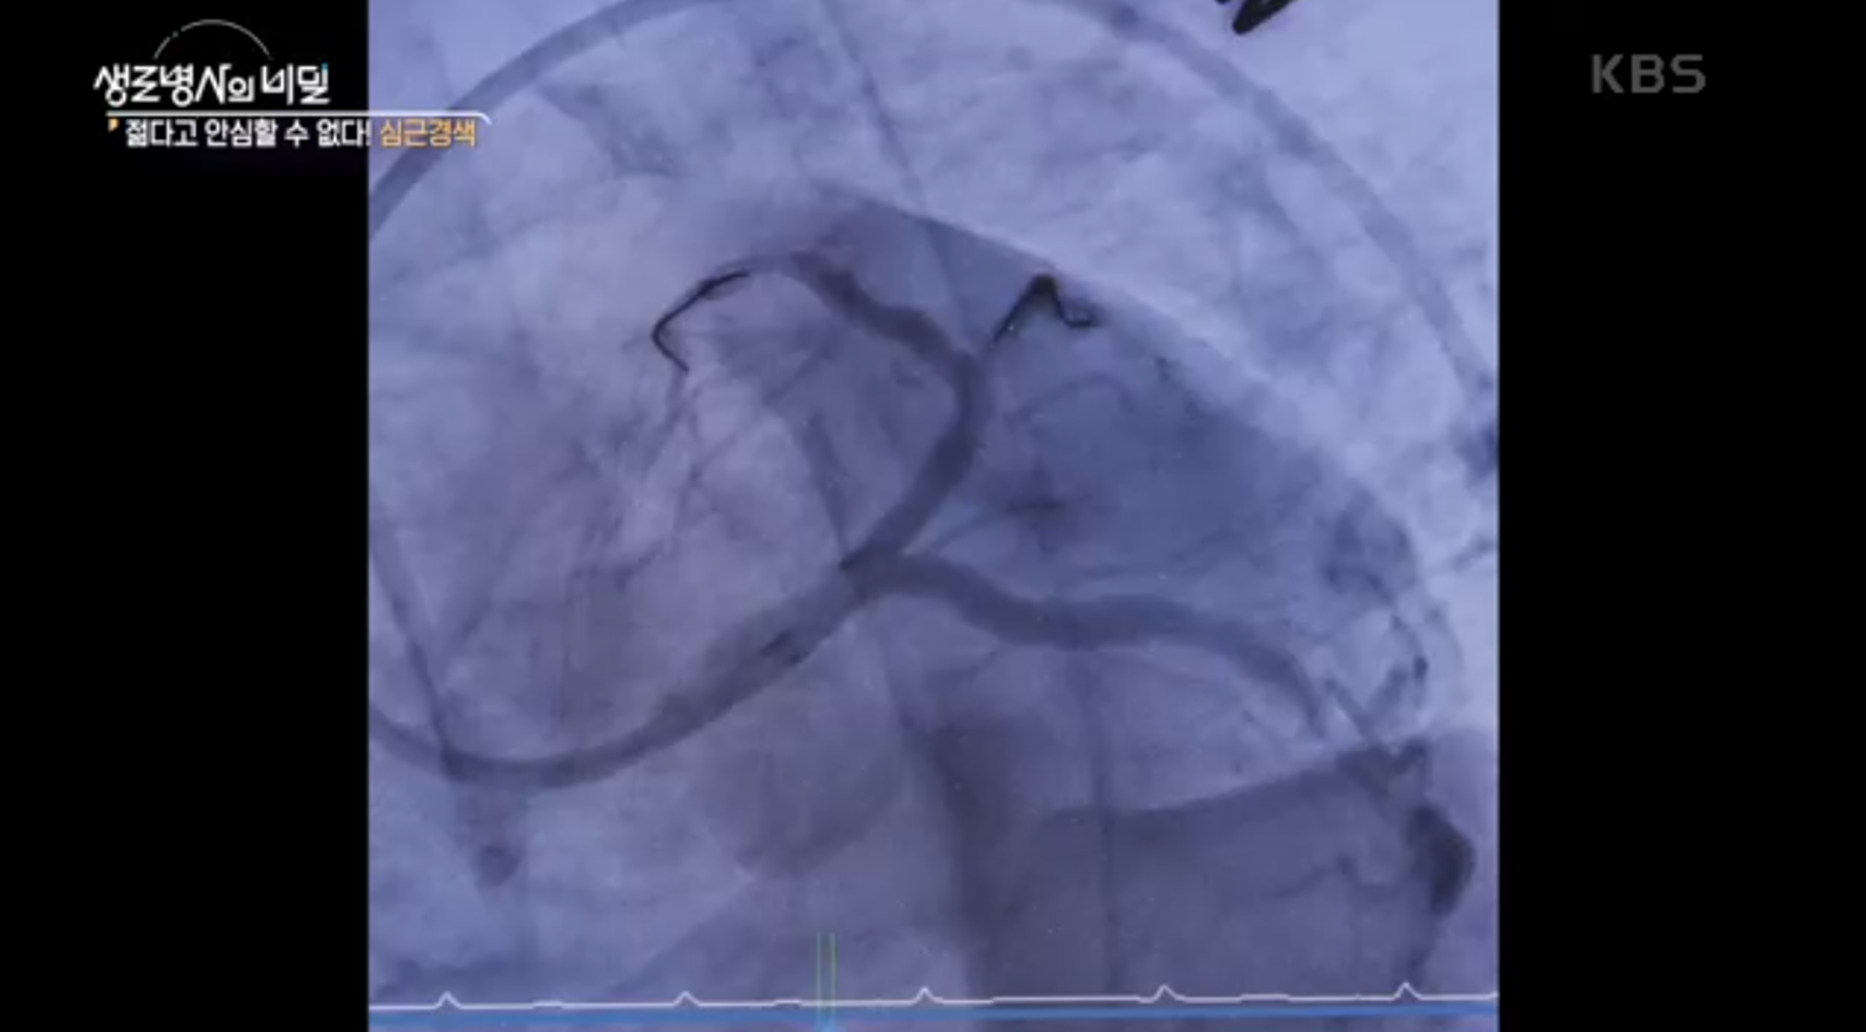

방송에서는 30대 남성이 테니스를 치다 갑자기 쓰러져 응급처치를 받는 사례가 소개되었습니다. 이 환자는 급성 심근경색으로 인해 응급실에서 수혈과 스텐트 시술을 받았습니다.

심근경색 초기 사망률은 약 30%로, 빠른 혈관 재개통이 생사에 직접적인 영향을 미칩니다. 스텐트 삽입술은 이 골든타임 내 필수적인 치료라는 점도 강조되었습니다.